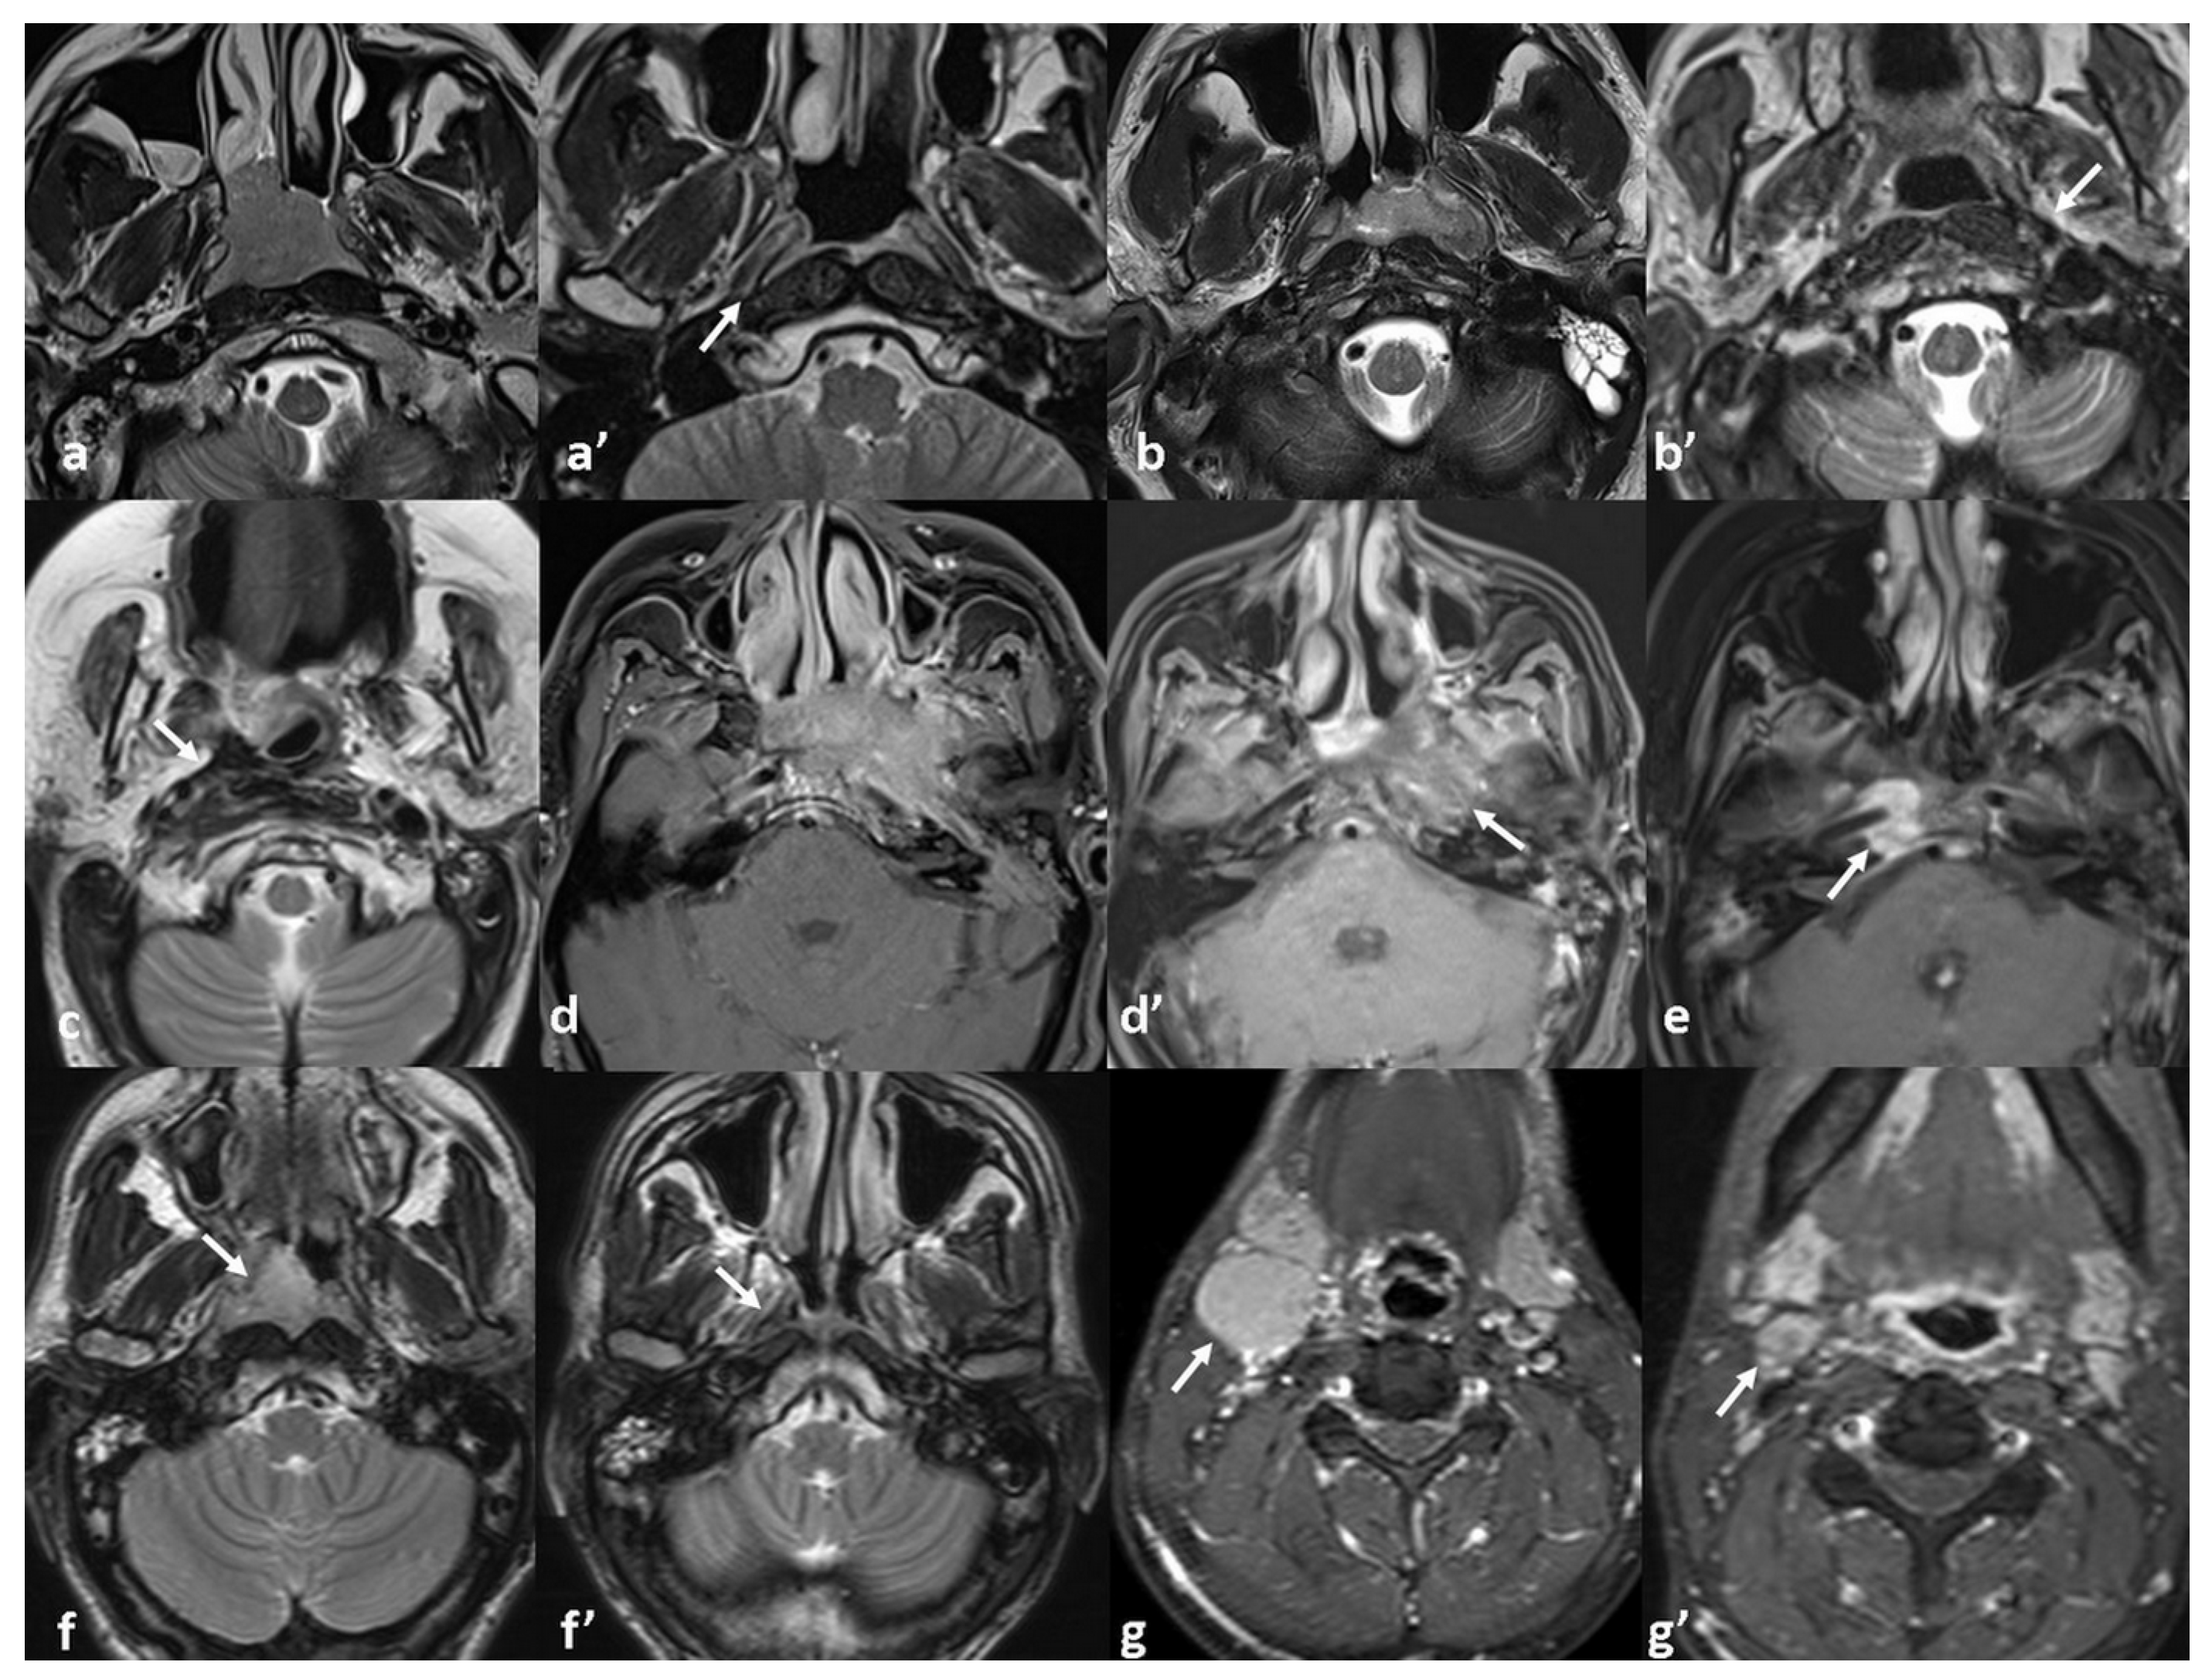

| MRI Response Patterns | Local Tumor Stage | Total | No Recurrence | Recurrence | Total | |||

|---|---|---|---|---|---|---|---|---|

| T1 | T2 | T3 | T4 | |||||

| Complete resolution without any sequel signal abnormality | 72% (n = 5) | 29% (n = 7) | 0% (n = 0) | 0% (n = 0) | 23% (n = 12) | 92% (n = 11) | 8% (n = 1) | n = 12 |

| Thin fibrosis at the primary tumor site | 14% (n = 1) | 21% (n = 5) | 36% (n = 4) | 0% (n = 0) | 19% (n = 10) | 90% (n = 9) | 10% (n = 1) | n = 10 |

| Bulky fibrosis without discernible soft tissue or enhancement | 0% (n = 0) | 21% (n = 5) | 46% (n = 5) | 10% (n = 1) | 21% (n = 11) | 73% (n = 8) | 27% (n = 3) | n = 11 |

| Heterogeneous signal with subtle contrast enhancement | 0% (n = 0) | 12% (n = 3) | 18% (n = 2) | 30% (n = 3) | 15% (n = 8) | 50% (n = 4) | 50% (n = 4) | n = 8 |

| Residual enhancing soft tissue | 0% (n = 0) | 0% (n = 0) | 0% (n = 0) | 60% (n = 6) | 12% (n = 6) | 17% (n = 1) | 83% (n = 5) | n = 6 |

| Complete resolution at the primary site with persistent nodal disease | 14% (n = 1) | 17% (n = 4) | 0% (n = 0) | 0% (n = 0) | 10% (n = 5) | 100% (n = 5) | 0% (n = 0) | n = 5 |

| Total | 100% (n = 7) | 100% (n = 24) | 100% (n = 11) | 100% (n = 10) | 100% (n = 52) | 73% (n = 38) | 27% (n = 14) | 100% (n = 52) |

| p < 0.001 * (tau-b = 0.43) | p = 0.004 * (χ2) | |||||||

| LN necrosis | 0.023 * | 0.443 | |

| Absent | 6/35 (17.1%) | ||

| Present | 8/17 (47%) | ||

| No. of Metastatic LN | 0.020 * | 0.031 * OR: 1.20 95%CI [0.02–0.43] | |

| No recurrence/recurrence | 5 (±0.8)/9 (±1.6) | ||